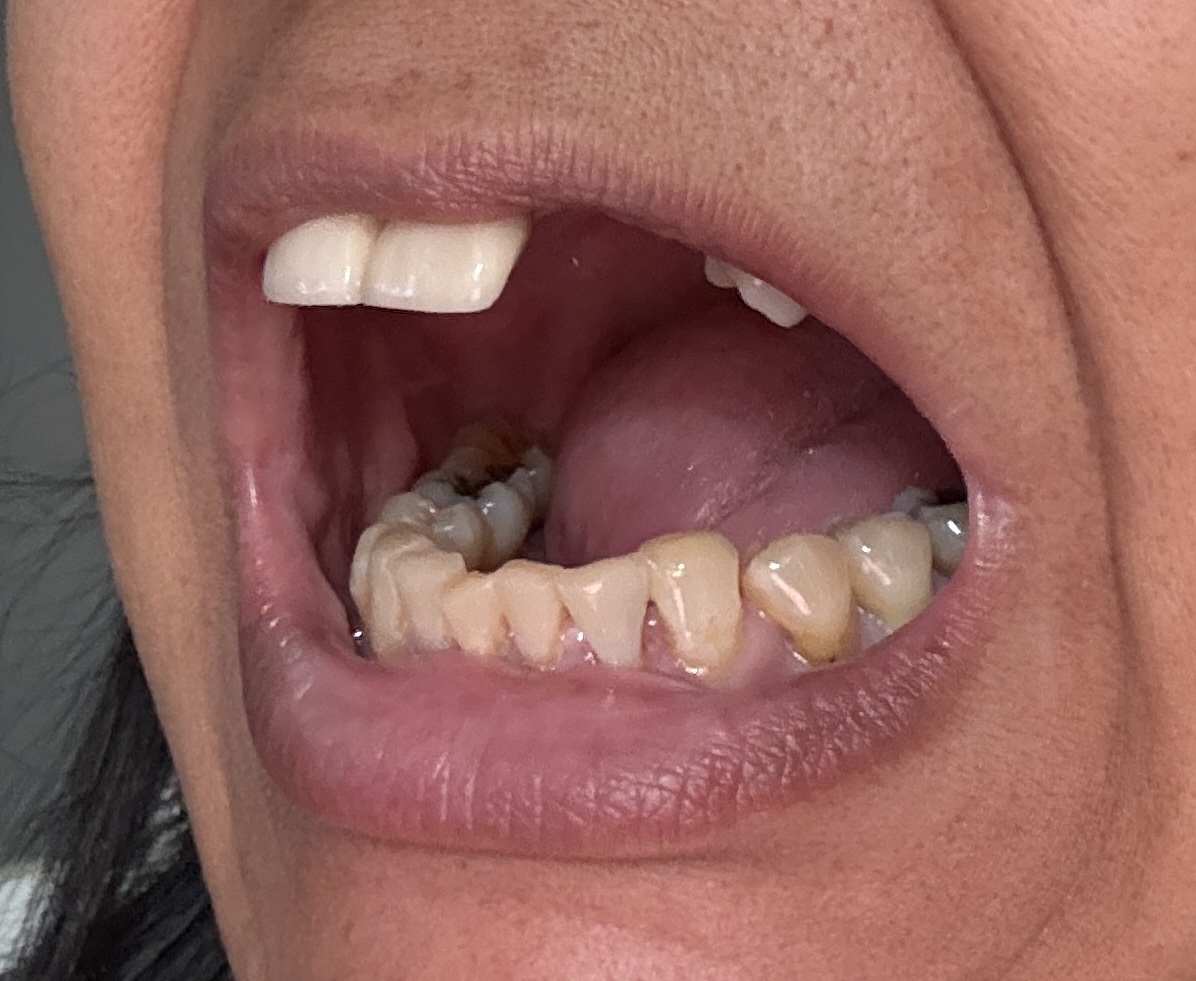

Overall information (upper arch)

12,13,14 have had root canals in past and now have quite a bit movement. 2-5 have all had root canals in past and now the crowns are breaking down.

Overall information (lower arch)

Overall, all of my gums have receded and most of the bottom teeth are exposed w/ some roots and there are many cavities.